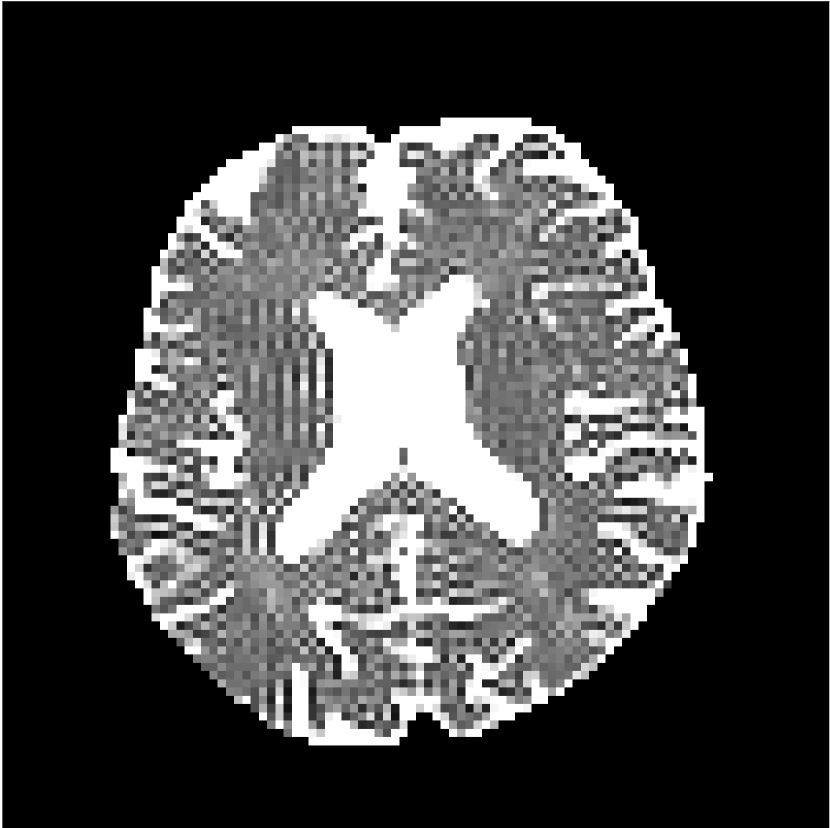

Figure 10 compares mean diffusivity maps across various partial Fourier factors between the CCNN and state-of-the-art methods.

No PF

7/8 PF

6/8 PF

5/8 PF

Figure 10: Comparison of mean diffusivity (MD) parameter maps across PF factors of 5/8ths, 6/8ths, 7/8ths, and without PF (No PF). The methods include state-of-the-art (SoA) and CCNN methods. Without partial Fourier, both methods are similar; however, as the PF factor increases, substantial artifacts are introduced in the SoA method, particularly around the lateral ventricles. The CCNN method is able to reduce the introduction of artifacts.

The methods perform similarly without partial Fourier acceleration, but as partial Fourier acceleration increases, the image is continually degraded in the SoA method, with "black voxels" appearing around the lateral ventricles. The CCNN method mitigates the appearance of these artifacts in the parameter maps.